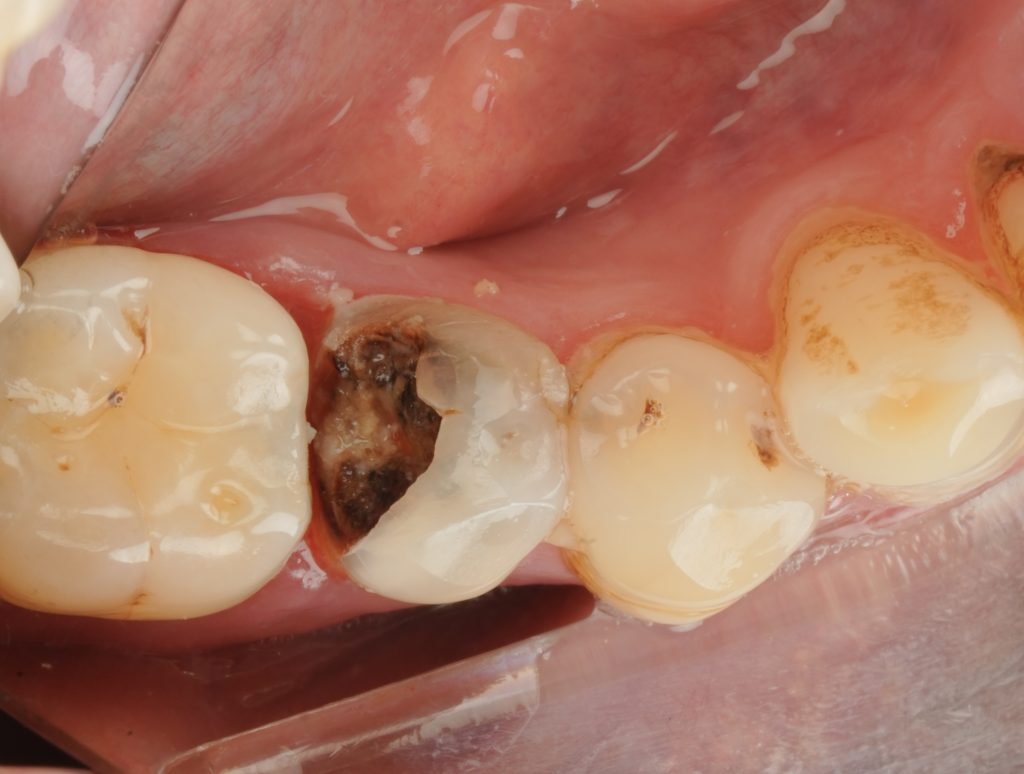

A patient presented with a previously root-filled maxillary premolar exhibiting secondary caries and a defective distal margin (Fig 1). Radiograph confirmed incomplete coronal sealing and intact periapical area. The plan included re-access, coronal reinforcement, and full cuspal coverage using composite.

- Fig 1: Pre-op radiograph showing distal caries in treated premolar.